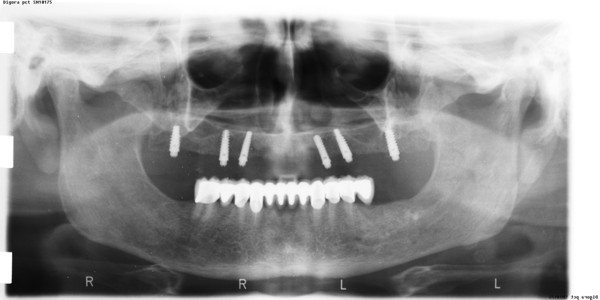

ABSTRACT La literatura oclusal se ha encargado de describir distintas funciones de la misma a través de los tiempos. El presente caso se realiza en forma de sobredentadura (over denture) debido a que la carencia de reborde óseo en el sector anterior verificado tanto clínicamente como mediante telerradiografía , impedía llevar a cabo una prótesis fija , por lo que se optó por un sistema de pilares ceramizados y paralelizados mediante el sistema SIRIUS, sobre seis implantes, y la conexión a una estructura de metal cerámica FIJA AMOVIBLE, mediante coronas telescópicas galvanizadas, otorgando al sistema la rehabilitación mediante una PIA(Prótesis Implanto Asistida con reposición ósea y gingival mediante porcelana rosa.) MATERIAL Y MÉTODOS: IMPLANTES:KLOCKNER SK-T.T.S. MONTAJE Y REGISTROS: ARCO FACIAL ESTÁTICO Y ARTICULADOR PRIMARIA: Abuttmets Ceramizados (I.P.S. D.SIGN IVOCLAR) SECUNDARIA: Cofias Galvanoformadas (AURO GALVAN CROWN WIELAND) TERCIARIA: Férula de Porcelana sobre Metal (I.P.S. D. SIGN IVOCLAR) CEMENTADO INTERFASE: NIMETIC CEM-ESPE DESARROLLO Se presenta el paciente a la consulta requiriendo la resolución de su maxilar inferior, el que se restaura mediante una férula de metal porcelana , en la que se preparan los lineamientos oclusales ideales (Spee-Wilson-Cuatro Niveles-etc) a fin de tener un sustrato de trabajo correcto, para la confección del maxilar superior, que porta una Prótesis Total convencional. Se estudia mediante Panorámica, Dentascan y Montaje en articulador semi ajustable. Se instalan seis implantes Klockner con Técnica Semisumergida pensados para una Carga diferida a tres meses después de la implantación Se realiza el arrastre de los Transfer mediante cubeta individualizada y fenestrada. Se confeccionan los abuttmentes correspondientes y se llevan a boca mediante una férula de posicionamiento realizada en Acrílico Duralay, el que por sus condiciones de carencia de cambios volumétricos verifican el correcto ajuste de los mismos Se ceramizan los abuttments y se paralelizan mediante el sistema SIRIUS, llevándolos a boca y chequeando su instalación Se confecciona una Prótesis Total Provisional que llevará el paciente durante el período de Osteointegración Se procede a la confección en laboratorio de las cofias galvánicas Sobre un nuevo modelo mayor se confecciona la férula de metal que uniremos en boca a las cofias galvanizadas mediante un cemento especial, una vez confeccionada la porcelana. Se prueba en boca la férula metálica, verificando su holgura que será ocupada por el cemento antedicho, y se comienza con el montaje de la cerámica y la verificación de los patrones oclusales de la misma. Se instala el todo haciendo morder al paciente con el medio cementante instalado. FIGURA 40 FIGURA 41 FIGURA 42 CONCLUSIONES La función de «GUIA CANINA», como esquema mas propicio para cumplir con los deseos de «autoprotección » de un SEG, rehabilitado o no, no se cumple al 100 % en casos como el presentado. La razones por las cuales el uso de la misma en lo que se da en denominar OCLUSIÓN MUTUAMENTE PROTEGIDA consiste en tres factores que detallo a continuación: A. En una función desoclusiva realizada por las piezas anteriores, como por ejemplo el canino, el BRAZO DE RESISTENCIA generado en la palanca desoclusiva, es por lo menos igual al brazo de potencia desarrollado, argumento de gran peso para hablar de la Desoclusión Canina como esquema de elección- B. La inclinación de los rebordes marginales del canino superior, esta dentro de los 70º, a diferencia de la tabla oclusal posterior que puede variar entre los 20 y 40 º. C. El estimulo que generan los dientes anteriores se dirige por via aferente al SNC, exitando por vía eferente, fundamentalmente al músculo temporal en sus fibras anteriores o VERTICALES…fibras de mucha menos capacidad de fuerza, que si la acción la ejercieran las fibras de la cincha PTERIGO MASETERINA, que serían exitadas en el caso de una Función de Grupo. EN EL CASO PRESENTADO LAS DOS PRIMERAS RAZONES TIENEN VIGENCIA. Sin embargo la última de ellas , al no tener los Implantes terminaciones nerviosas como las que posee el periodonto , los estímulos que llegan al SNC no se cumplen, y por lo tanto no existe la respuesta que por conducción eferente estimularía al músculo temporal a su acción. De la misma manera, el hecho que estos Implantes estén ferulizados , trasmite fuerzas laterales también a los posteriores, y no solo a los que actúan como caninos. El beneficio de las dos primeras razones de uso de una Función Canina en un caso como este, obedece a que de por si las mismas minimizan la acción direccional de las fuerzas, las que sin embargo son compartidas por las piezas posteriores tanto del LT como del LnT. En este compartir de la función, me resulta conveniente denominar a este esquema: FUNCIÓN DE GRUPO POSTERIOR DE ACCIÓN CANINA. ———————————————————————————————————- PIE DE FOTOS: 37: CASO TERMINADO